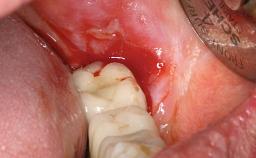

Retreatment of a Patient with Multiple Biological and Technical Complications and Failures

A 66-year-old patient presented because of retention loss of the tooth-supported FDP in the right maxilla (x-13-x-11). The mandibular full-arch implant-supported reconstruction (x-i34-i33-x-x-x-x-i43-i44-x) had suffered extreme wear. His medical history revealed high blood pressure, controlled with anti-hypertensive medication. The patient was a light smoker (2 to 3 cigarettes per day). The existing reconstructions had been performed alio loco about five years previously. That treatment had taken an extensive amount of time, and as early as during the fabrication of the reconstructions, multiple complications had occurred with the provisionals.